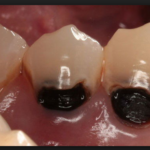

Кариес корня зуба фото

Кариес на корне зуба визуально практически никогда не определяется. Очень редко, и лишь в случаях, когда зубной камень значительно опустил ткани десны, может быть видно темное пятно или изъязвленный участок эмали. Чаще всего кариесом развивается на корнях передних нижних зубов и в межзубном промежутке. Во втором случае можно заметить снижение высоты десневого сосочка и увеличение межзубного промежутка в самой нижней его части.